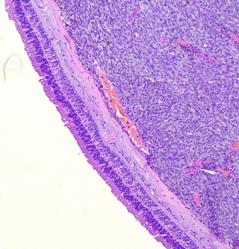

Examen microscópico: Los cortes histológicos exhiben proliferación de células neoplásicas con dos morfologías: unas de aspecto epiteloide de núcleos redondeados y nucleolos acidófilos prominentes, alternan con nidos de células fusadas. Se advierte pigmento melánico en células dispersas y abundante pigmento en áreas de necrosis tumoral. El tumor infiltra tejido adiposo y conectivo circundante. Se observa epitelio conjuntival sin alteraciones.

Mitosis: escasa a moderada cantidad. Necrosis: Presente.